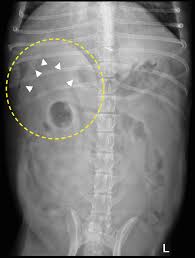

Exocrine pancreatic cancer is very rare in dogs (<0.5% of all cancers) and uncommon in cats. Some dogs have signs that. Insulinoma is the most common endocrine pancreatic tumour. Jaundice is yellowing of the eyes and skin. Ct should be done before ercp and insertion of an endoprosthesis on the left a pancreatic tumor in direct contiguity with the confluens of the portal and superior mesenteric vein. Postoperative survival time for dogs which died or were euthanased as a direct result of tumour recurrence, and time to recurrence of clinical signs. There is no known underlying cause. In dogs, most tumors that grow on the pancreas are malignant. Symptoms, diagnosis & treatment | week 1. Pancreatic disease in dogs is not so common as other diseases but is the consequence of many other diseases. Learn about msk's program for people with pancreatic cysts that need to be watched carefully over time for signs of cancer. Oral tumors in dogs are most often malignant. Signs of pancreatic cancer in dogs pancreatic tumors pancreatic cancer (adenocarcinoma) in dogs pancreatic cancer (insulinoma) in dogs pancreas cancer in dogs how long can a dog live with pancreatic cancer?